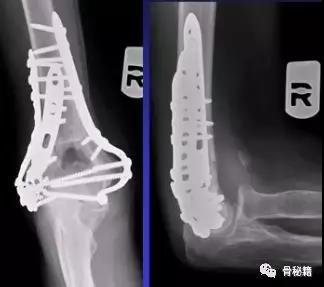

适当的固定技术原则

1、最大限度地固定远端碎片2、确保远端节段的所有固定有助于提高髁间水平的稳定性3、不建议使用三分之一管型板,因为它们太弱的并易于断裂,尤其是在粉碎干骺端

4、钢板长度也很重要:板应在近端以不同水平,以避免在肱骨干骨中形成应力集中

5、解剖锁定钢板板通过卓越的生物力学特性提供更好的临床疗效

6、良好的固定需要两个板,平行or垂直?在肱骨远端骨折中,一块钢板通常不足以保证良好的稳定性,而在其他骨折(例如,胫骨近端和股骨远端)中,LCP的引入消除了对双柱固定的需要。应谨慎使用单侧钢板板,仅在单柱损伤的情况下可以应用。

7、钢板如何搭配?迄今为止,通常使用前两种钢板的固定。AO推荐在治疗中应用垂直钢板。然而,这种方法受到了广泛的批评 - 主要是因为通过后外侧板难以获得足够的螺钉数量和前后方向的长度的螺钉固定。与垂直钢板相比,平行板配置似乎提供了更好的生物力学性能。实在不行的时候再用三钢板技术

固定的八个细节:1、每个螺钉都应该经过钢板固定2、每个螺钉固定骨折块的螺钉,在他的对侧应该也有一个钢板的把持3、在远端一定要打满螺钉4、每个螺钉要尽可能的长5、每个螺钉需要尽量的对关节面的骨块进行固定6、螺钉应通过交叉锁定在一起,从而形成角稳定结构并将内外侧柱连接在一起7、钢板需要再髁间完成加压8、所使用的板必须足够坚固并且足够坚硬以抵抗在髁上水平处的断裂或弯曲。